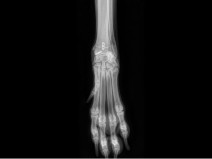

• 19ème Cours de Propédeutique, sémiologie et pathologie de l'appareil locomoteur : Carpe, tarse et au-delà : explorons les extrémités

Le thème de cette 19ᵉ édition du Cours de Propédeutique, Sémiologie et Pathologie de l’Appareil Locomoteur à Bédoin sera d’explorer les extrémités. Nous poursuivons l’objectif qui fait la force de ce rendez-vous depuis ses débuts : offrir une approche à la fois rigoureuse, pratique et actuelle des affections locomotrices. À travers un programme structuré mêlant rappels fondamentaux, analyse sém...

Orthopédie

Traumatologie